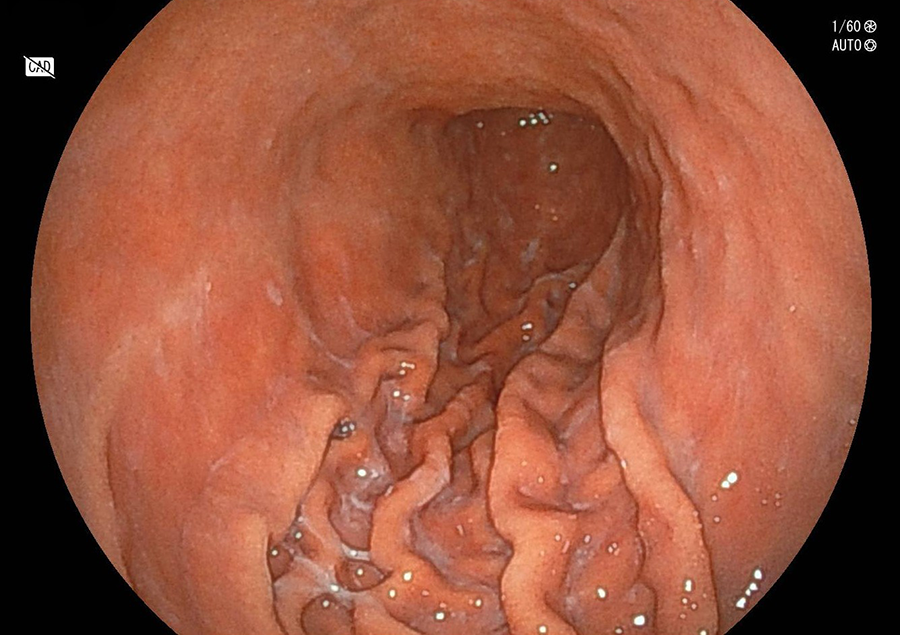

鳥肌胃炎

ピロリ菌に感染すると、まず胃の出口付近から炎症が始まり、胃全体に広がっていきます。これは胃の出口付近(前庭部)にピロリ菌に対する免疫反応によってリンパ球がたくさん集まり、このようにブツブツした粘膜になります。これを「鳥肌胃炎」とよび、スキルス胃がん発生のリスクが高いといわれます。